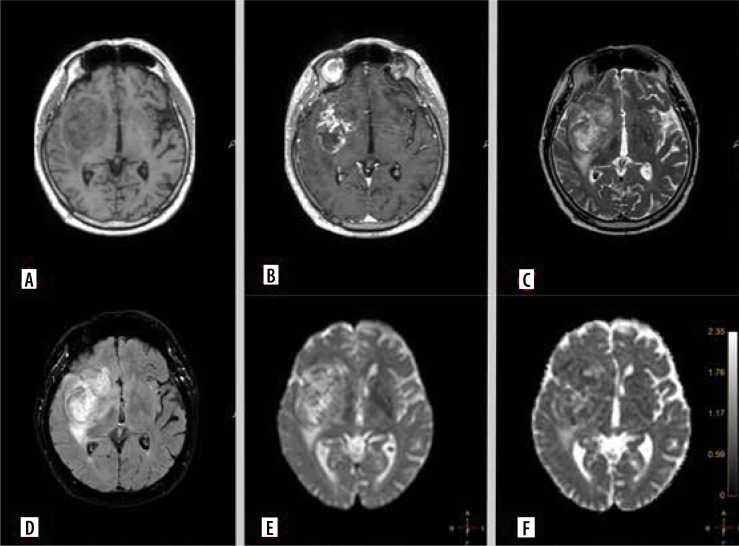

Material and methods: A total of 91 glioma patients treated between August 2023 and March 2024 were included in the analysis. All patients underwent preoperative magnetic resonance imaging (MRI), including DWI, and had available histopathological and genetic test results. Clinical data, tumour characteristics, and genetic markers such as IDH1 mutation, MGMT promoter methylation, EGFR amplification, TERT pathogenic variant, and CDKN2A deletion were collected. Statistical analysis was performed to identify correlations between ADC values, MRI perfusion parameters, and genetic characteristics.

Results: Significant associations were found between lower ADC values and aggressive tumour features, including IDH1-wildtype, MGMT unmethylated status, TERT pathogenic variant, and EGFR amplification. Additionally, distinct ADC patterns were observed in gliomas with CDKN2A, TP53, and PTEN gene deletions. These findings were further supported by contrast enhancement and other MRI parameters, indicating their role in tumour characterisation.